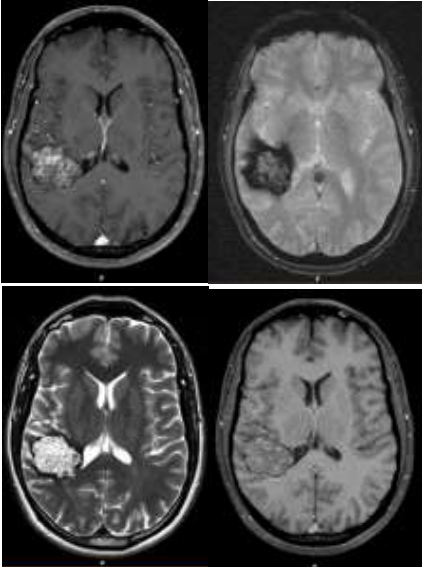

Paciente do sexo masculino, 40 anos, tabagista, apresentando episódio único de crise convulsiva tônico-clônica generalizada. Sem antecedentes de doença neurológica familiar. Encaminhado pelo neurologista assistente para investigação complementar com exames de imagem, que demonstrou os achados abaixo.

Baseado na história clínica e exames de imagem, assinale a alternativa correta.